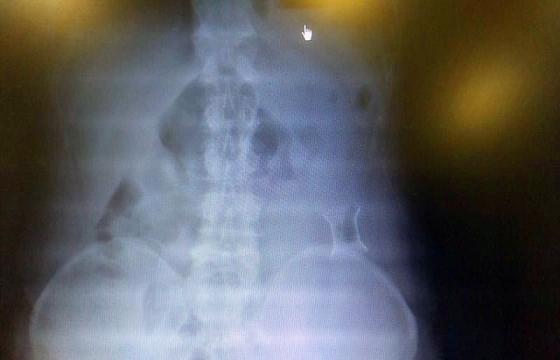

受試患者在結(jié)腸端端吻合術(shù)中,使用我司新研制產(chǎn)品達(dá)到了理想的預(yù)期效果。患者術(shù)后7天、14天X光片顯影,可降解腸道支架均能按研制設(shè)計(jì)的預(yù)期時(shí)間節(jié)點(diǎn)保持應(yīng)有強(qiáng)度,術(shù)后21天X光片顯示可降解腸道支架已完全破碎,并排出體外。在整個(gè)試驗(yàn)過程中,病患無(wú)任何不良反映,耐受良好。